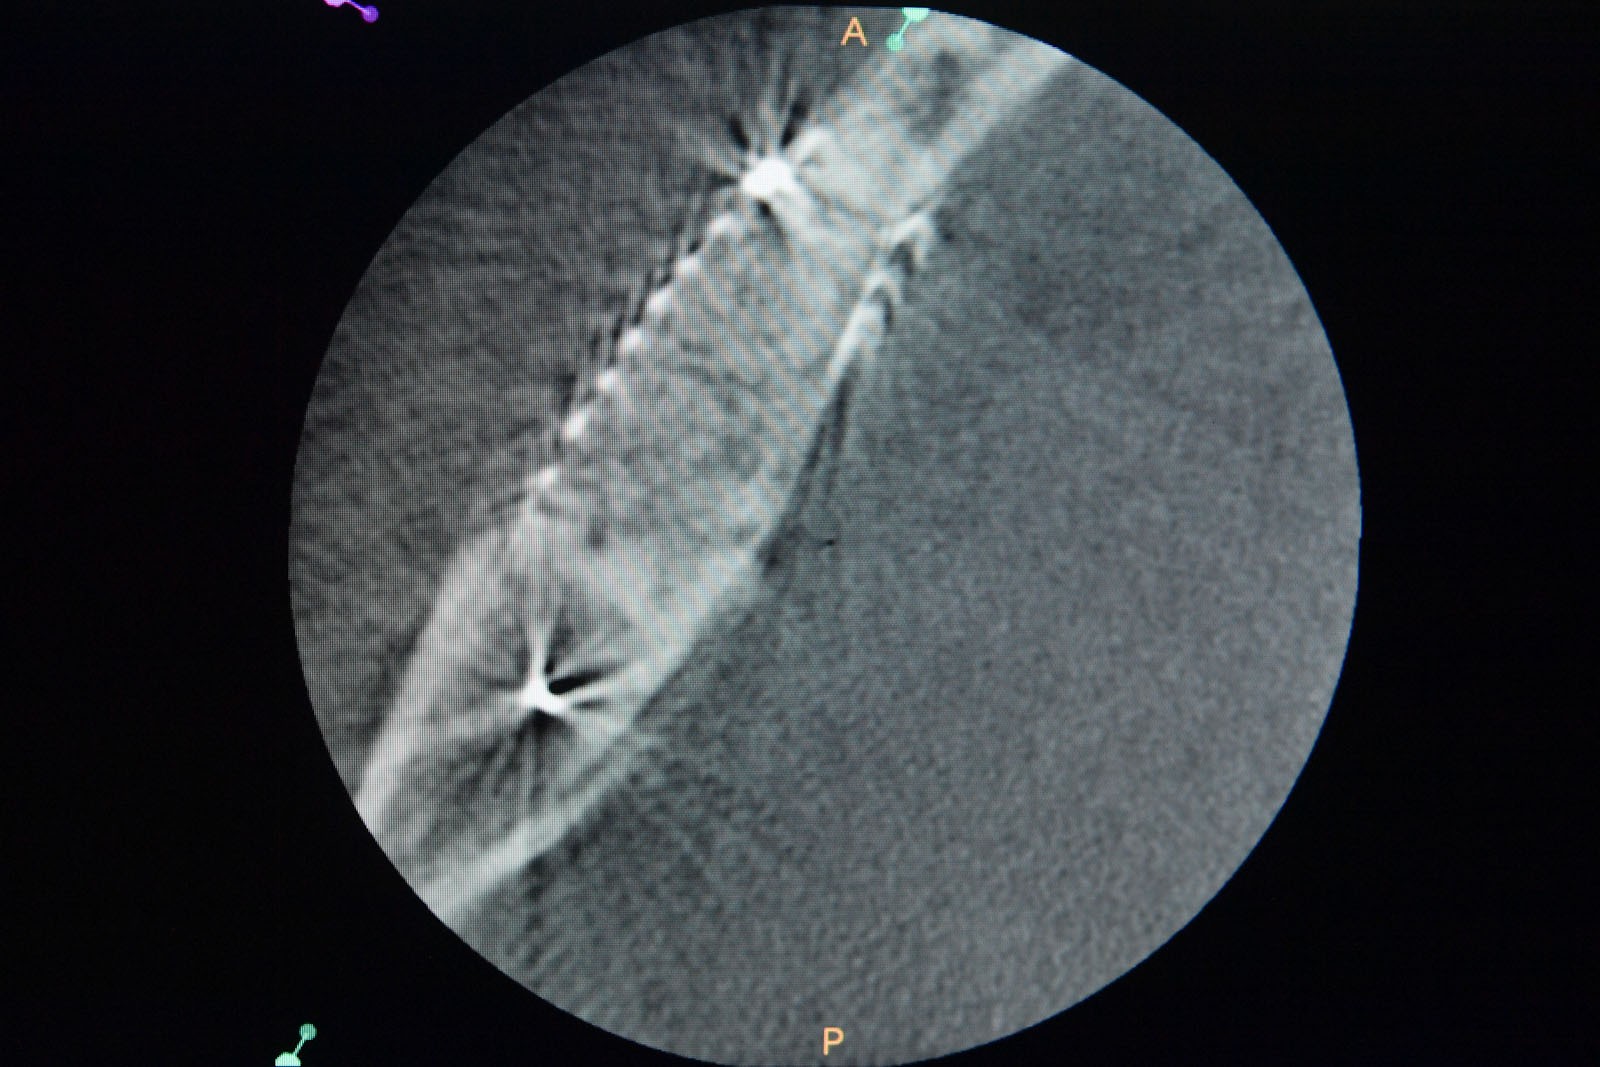

Przed podjęciem leczenia należy określić stopień zaniku kości szczęk oraz żuchwy. W tym celu przeprowadza się badanie kliniczne oraz odpowiednią diagnostykę obrazową pacjenta. Uwzględnia ona zdjęcie panoramiczne OPG jako podstawę dwuwymiarowego obrazowania podłoża kostnego oraz możliwe jest badanie tomograficzne CT lub bardziej precyzyjna tomografia stożkowa CBCT. Opcjonalnie wykorzystywana diagnostycznie tomografia pozwala na bardziej wnikliwą ocenę stopnia zaniku kości w trójwymiarowym, przestrzennym obrazie.

Precyzja projektu druku siatki bazuje na dokładności odwzorowania kształtu kości w stożkowej tomografii komputerowej CBCT, co zapewnia ich dobre przyleganie do podłoża kostnego oraz ogranicza powstawanie powikłań w postaci obnażania się siatek.